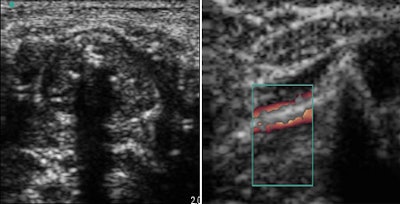

| Ultrasound confirmed the trachea (left) and the glottic plan (right). |

According to the results, the trachea was always identified on sonography by the tracheal rings. Also, the glottic plan was characterized by the visualization of the vocal cords, which moved during respiration. Finally, tracheal intubation provided enhanced shadowing posterior to the tracheal ring.